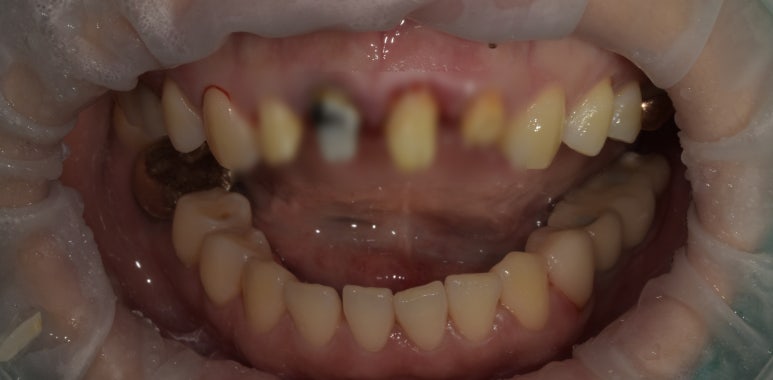

앞니브릿지교체 치료 전

2023-04-10

오래 전 앞니 4개를 브릿지로 치료하셨는데,

보철물이 오래되기도 했고 기존에 신경치료했던 치아가 변색되고 잇몸이 내려앉으면서

보철물의 경계 부분이 노출되어 보기도 좋지 않은 상태라 교체가 필요했습니다.

이런 경우 하나의 치아만 문제가 생겼다고 하더라도 브릿지는 하나의 세트여서 전체 다 교체를 해주어야 하기 때문에

환자분께서 나중을 생각해서라도 싱글 크라운으로 제작을 원하셨습니다.